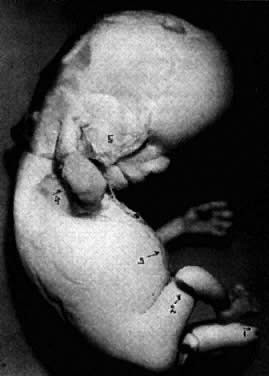

Fig. 17. Malformed embryo at the end of 10th gestational week. Multiple malformations are caused by bleeding into amnionic cavity from the ruptured umbilical vein near abdominal insertion of umbilical cord. 1, amputation of left leg; 2, fibrin band constricting right thigh; 3, fibrin band between the ruptured vein and mandible; 4, right hand fixed to the blood cloth covering the right pinna.